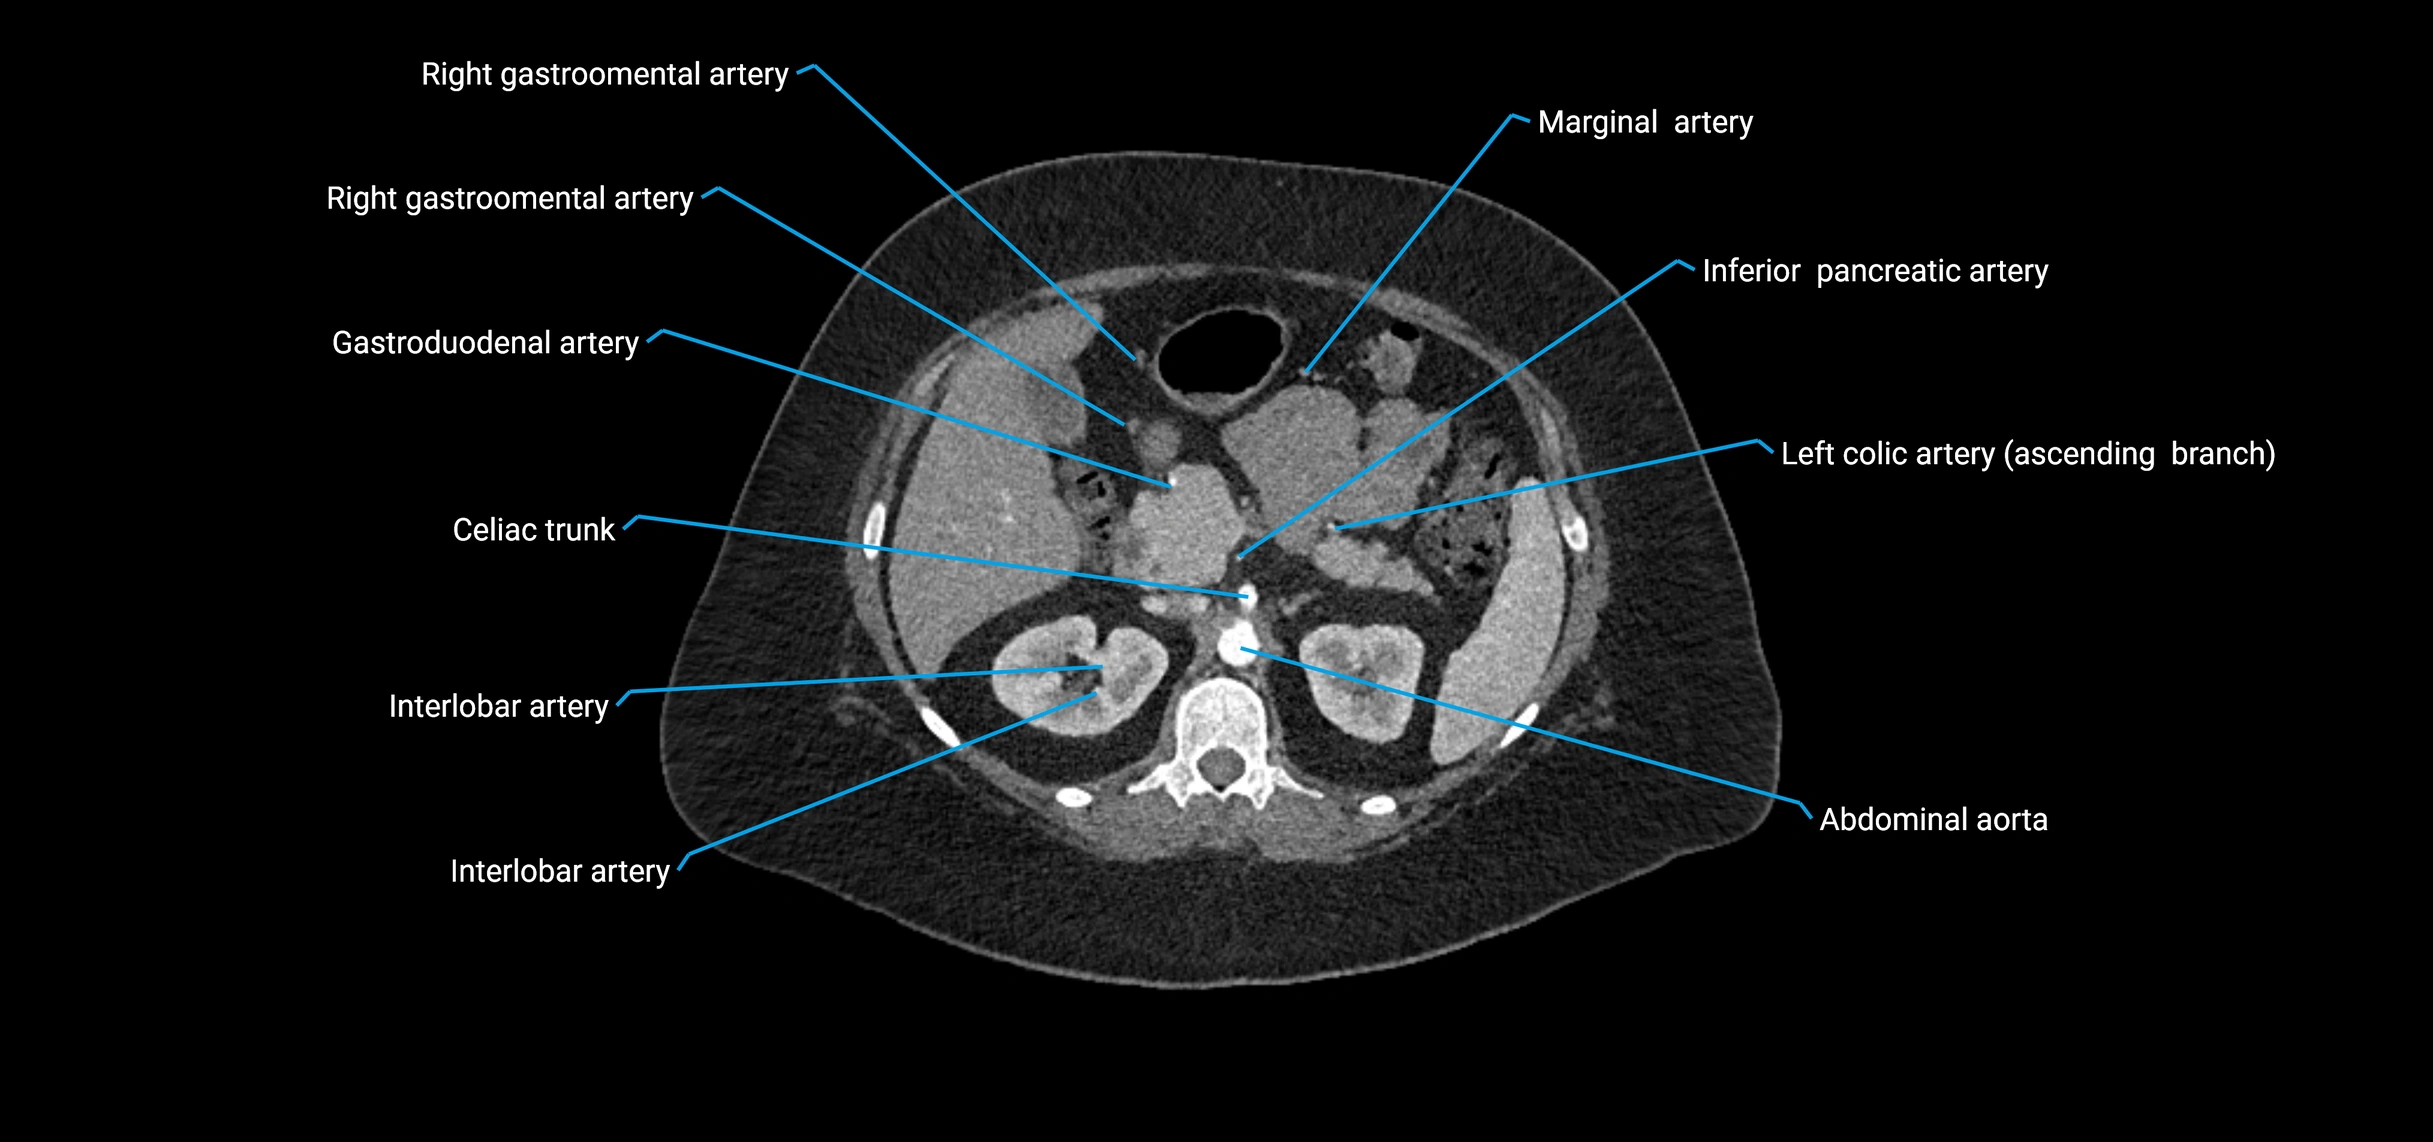

CT images

image

Contrast-enhanced CT (CTA):

• Gold standard for abdominal aortic imaging

• Provides excellent detail of lumen, wall, aneurysm, thrombus, and branch vessels

• Multiplanar and 3D reconstructions help in aneurysm measurement, stent graft planning, and dissection evaluation

• Detects acute rupture, traumatic injury, or occlusion with high sensitivity